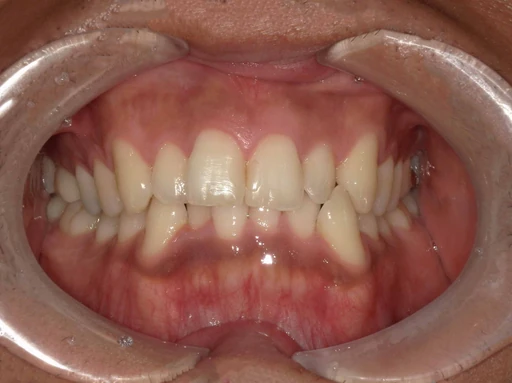

症例2

こちらは、インビザラインによる矯正治療の症例です。

治療前は歯並びの乱れが見られましたが、マウスピースを段階的に交換しながら歯を動かすことで、見た目だけでなく噛み合わせも改善しました。

インビザラインは、目立ちにくく取り外しが可能なため、日常生活への影響を抑えながら治療を進められるのが特長です。